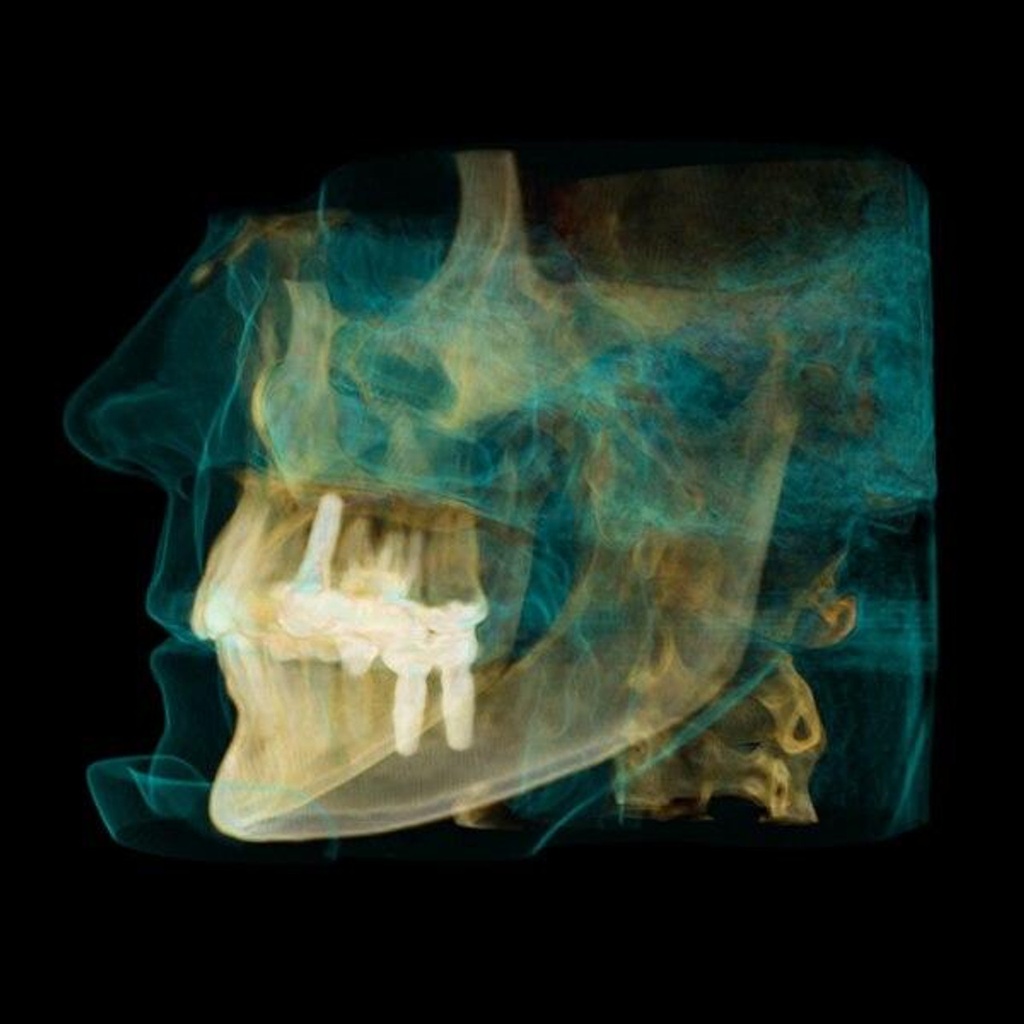

Introducing the CS 9300 Premium Panoramic, Cephalometric, and Cone Beam System from Carestream Dental – your ultimate solution for top-quality dental imaging. This state-of-the-art machine offers both 2D panoramic and cephalometric dental X-rays, as well as adjustable 3D cone beam images in up to seven different field of view sizes, extending up to 17x13.5 cm. This comprehensive range of imaging capabilities makes it a versatile tool, perfect for supporting a wide array of dental, surgical, or orthodontic examinations.

With the CS 9300 Premium, you can expect unparalleled image clarity and precision, allowing you to confidently diagnose and plan treatments with ease. Whether you're performing routine dental check-ups, complex surgical procedures, or orthodontic assessments, this system ensures outstanding results.

The CS 9300 is a multimodality imaging system that offers a wide range of 2D and 3D imaging options.

The CS 9300's 2D panoramic x-ray imaging capabilities are powered by variable focal trough technology, which provides optimal clarity for every image. The system's 3D imaging capabilities are based on cone beam technology, which delivers high-resolution images with a low radiation dose.